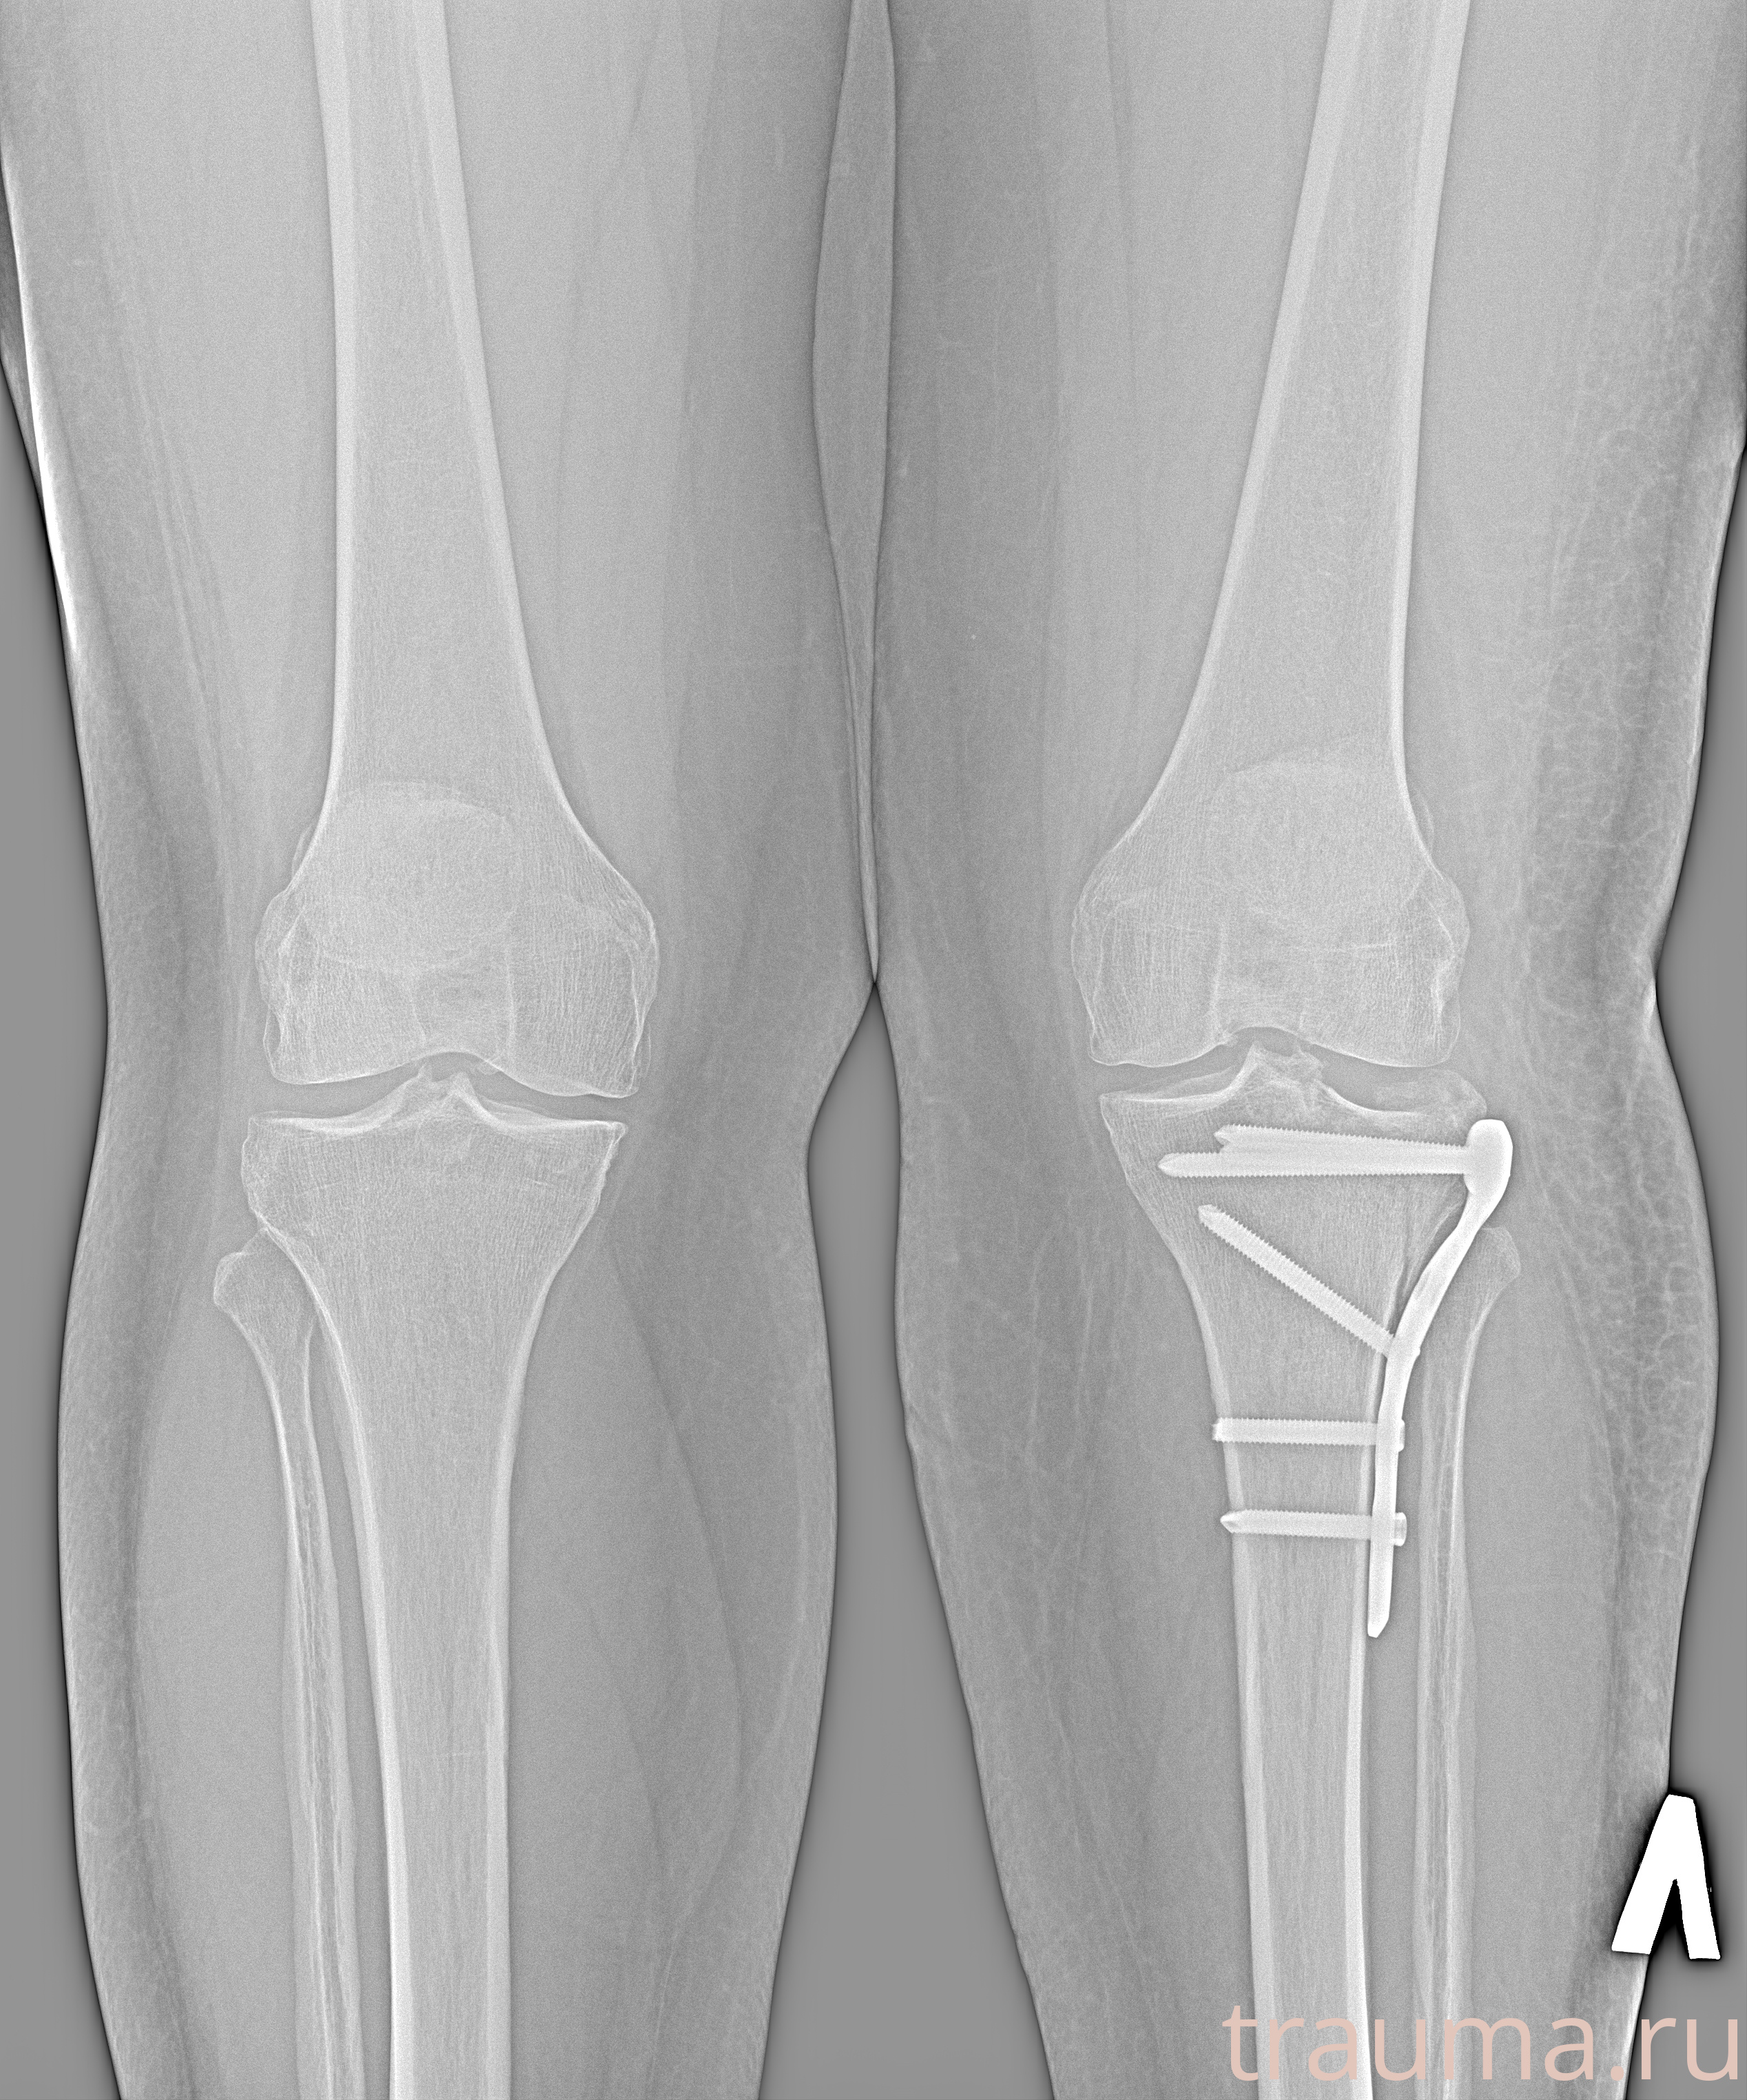

Рентгенограммы

Рентген на дому: по вашему адресу приезжает врач-рентгенолог, травматолог-ортопед с мобильным рентгеновским аппаратом, проводит диагностику травмы или заболевания, делает необходимые рентгенограммы, дает рекомендации по дальнейшему лечению. Получить качественные снимки в домашних условиях возможно благодаря уникальной методике, разработанной МосРентген Центром для института  Склифосовского